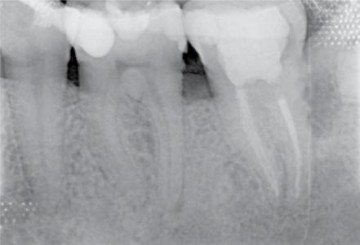

Postoperative x-rays: The endodontic treatment is performed after scouting of the root canal with a diameter 10 hand file and securing of the mesial root canals using the NiTi file One G. Shaping was carried out with TS1 and TS2 to the working length, the MB2 canal was prepared using…